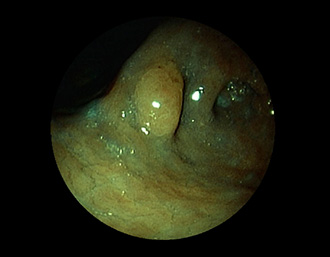

症例2:胃がん(66才男性)

術後胃(B-Ⅱope magen:十二指腸潰瘍手術)。吻合部の後壁側、軽度陥凹の白色病変を認める。生検:Group 5、Signent-ring cell carcinoma(印環細胞癌)と診断[早期胃癌]。高次医療機関へ紹介となり、残胃全摘術(リンパ節郭清)を行いました。

(通常画像)